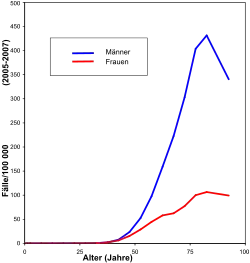

Epidemiologie

25 Prozent aller bösartigen Tumoren (Malignome) sind Bronchialkarzinome. Beim Mann ist es weltweit die häufigste Krebsart; in Deutschland nach dem Prostatakarzinom und dem kolorektalen Karzinom die dritthäufigste. Als Ursache von Krebssterbefällen liegt es bei Männern auf Platz eins, bei Frauen auf Platz zwei.[6] Die Inzidenz liegt in Mitteleuropa bei etwa 60 pro 100.000 Einwohner. Die Zahl der Neuerkrankungen – in Deutschland etwa 50.000 pro Jahr – weist eine steigende Tendenz auf. Unter den Todesursachen in Deutschland nimmt es mit rund 40.000 Todesfällen im Jahr die vierte Position ein, bei Männern gar die dritte.[7] Der Altersgipfel der Erkrankungen liegt um das 60. Lebensjahr. Die durchschnittliche Fünfjahresüberlebensrate (d. h., wie viele Erkrankte nach fünf Jahren noch leben) beträgt bei Männern 15, bei Frauen 20 Prozent.[6] Die Lebenserwartung des einzelnen Patienten ist aber sehr stark vom Stadium der Erkrankung (TNM-Klassifikation) und dem Subtypus (siehe unten) abhängig.

Eine zunehmende Häufigkeit bei Frauen wird beobachtet; auch bei Frauen in Europa wird Lungenkrebs bald die häufigste Krebstodesursache sein, in Großbritannien und Polen ist dies schon der Fall.[8] Das Verhältnis von erkrankten Männern zu Frauen liegt bei etwa 3:1, wobei es auf Grund der Änderung im Tabakkonsumverhalten von Frauen immer mehr zu einer Angleichung kommt (siehe Diagramm). Bedeutsam können Umwelteinflüsse oder genetische Ursachen sein, die Prognose ist bei Frauen etwas besser. Der Nichtraucher-Lungenkrebs ist bei Frauen häufiger als bei Männern.[9] Auch in den USA war die Lungenkrebsrate bei Männern stets höher als bei Frauen. Eine neuere Erhebung zeigt allerdings, dass bei jungen weißen US-Amerikanern die Lungenkrebs-Inzidenz bei Frauen über der von Männern liegt. Dies ist allein mit dem Rauchverhalten nicht hinreichend erklärbar.[10]